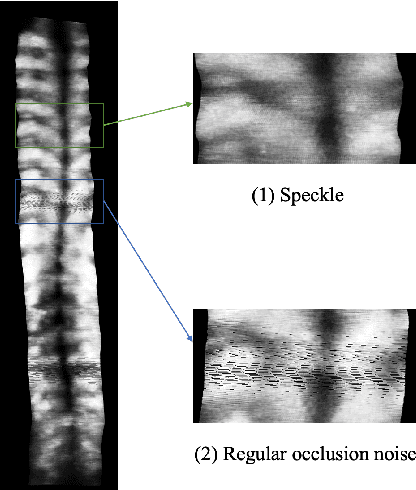

Abstract:3D ultrasound imaging shows great promise for scoliosis diagnosis thanks to its low-costing, radiation-free and real-time characteristics. The key to accessing scoliosis by ultrasound imaging is to accurately segment the bone area and measure the scoliosis degree based on the symmetry of the bone features. The ultrasound images tend to contain many speckles and regular occlusion noise which is difficult, tedious and time-consuming for experts to find out the bony feature. In this paper, we propose a robust bone feature segmentation method based on the U-net structure for ultrasound spine Volume Projection Imaging (VPI) images. The proposed segmentation method introduces a total variance loss to reduce the sensitivity of the model to small-scale and regular occlusion noise. The proposed approach improves 2.3% of Dice score and 1% of AUC score as compared with the u-net model and shows high robustness to speckle and regular occlusion noise.